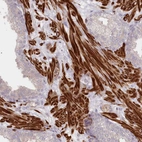

Immunohistochemical staining of human cerebral cortex shows moderate cytoplasmic positivity in neurons.